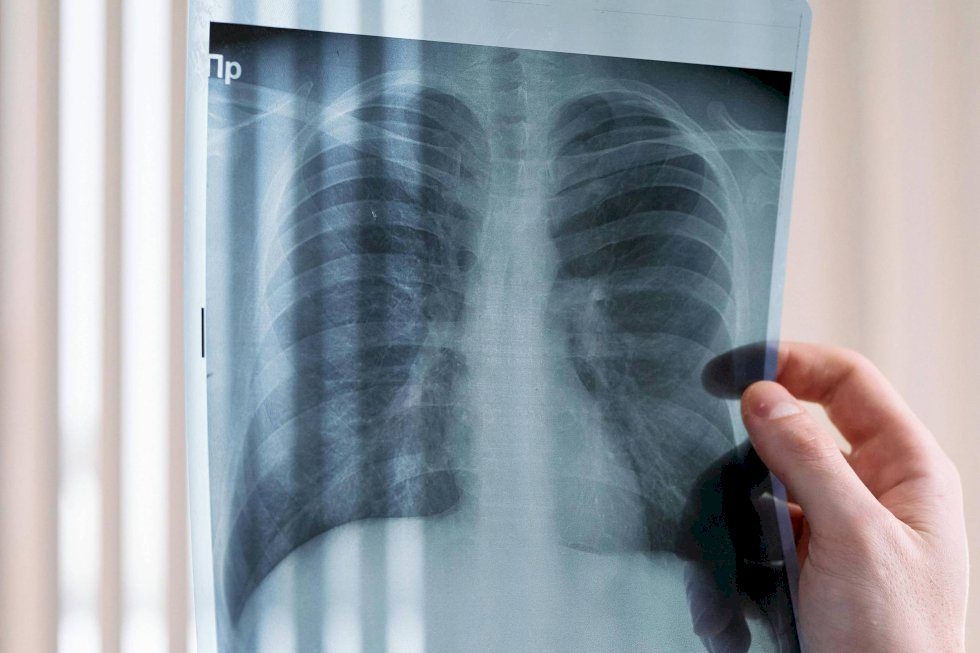

A Anvisa (Agência Nacional de Vigilância Sanitária) aprovou na segunda-feira (30) o uso do serplulimabe –vendido sob o nome comercial de Olizu–para tratamento de pacientes adultos com câncer de pulmão de pequenas células –subtipo que cresce mais rápido e tem alta capacidade de se espalhar.

Este tipo de câncer se desenvolve de forma mais rápida e tem uma maior tendência a se espalhar para outras áreas do corpo. Apesar de ser grave, as chances de cura aumentam significativamente com o diagnóstico precoce. O tabagismo é a principal causa do câncer de pulmão de pequenas células, responsável por cerca de 80% dos casos.